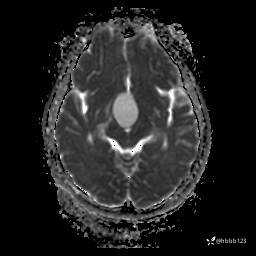

DWI:

ADC: